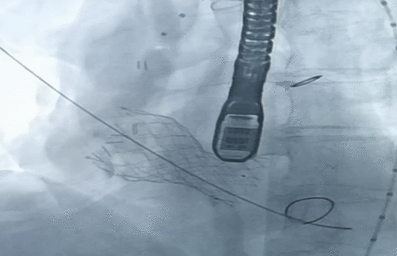

瓣膜释放完成

在影像、超声的共同指引下,术者团队通过调整输送系统至最佳位置实现精准释放,患者跨瓣压差即刻显著下降。再行主动脉造影提示瓣膜置入位置良好、形态完整,超声提示未见明显瓣周漏。术中及术后未出现相关并发症,圆满取得此次手术成功。